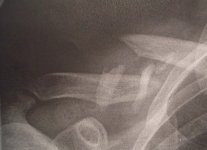

Två bilder. En skönhet och ett trasigt nyckelben. Tyvärr hade de datorstrul så de kunde inte skriva ut röntgenplåten de tog efter operation.

Zilversurfer skrev:Ungefär som mitt jävla nyckelben, efter 4 månader har skiten inte läkt ännu!!! Har växt helt fel, knakar & knastrar - och sticker upp 2 cm. Nu pratar läkarna om att knäcka upp benet och lägga det tillrätta. Varför i h***ete gjorde dom inte det direkt!!!!

Fy tusan vad kass. Jag är mer och mer glad över att jag slog sönder skiten ordentligt så att de opererade. Frågan är bara vad man ska göra med skrotet - sitta kvar eller ta ut?Zilversurfer skrev:Ungefär som mitt jävla nyckelben, efter 4 månader har skiten inte läkt ännu!!! Har växt helt fel, knakar & knastrar - och sticker upp 2 cm. Nu pratar läkarna om att knäcka upp benet och lägga det tillrätta. Varför i h***ete gjorde dom inte det direkt!!!!

Eftersom man inte kan köra så kraschade jag in i Esset igår, på andra varvet så att man inte drar ut på det i onödan. Hojen klarade sig ganska ok men mitt nyckelben gick i fyra bitar som valde fyra olika riktningar att peka åt.